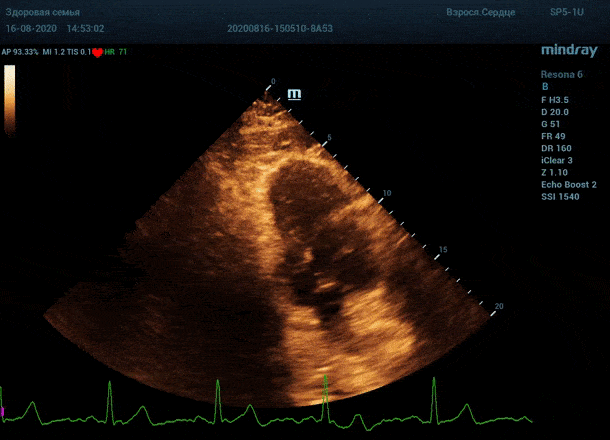

Обзор функции УЗИ: адаптивный колорайзинг

Глаз каждого человека по своей природе уникален. Одни люди лучше видят белый и серый цвет, прекрасно различают все его оттенки. Другим людям проще ориентироваться в голубом, синем и фиолетовом диапазоне, холодных тонах изображения. Однако большинство прекрасно видит оранжевый цвет, и очень четко отличает его от черного – анэхогенного пространства.

Адаптивный колорайзинг - настоящая находка для опытного врача ультразвуковой и функциональной диагностики. Для тренированного глаза открывается новый мир четких контуров, совершенно другой взгляд на привычные структуры сердца.

Данная функция присутствует в большинстве моделей Mindray, с возможностью эхокардиографического исследования. Ограниченное ЭХО окно можно победить разными путями.